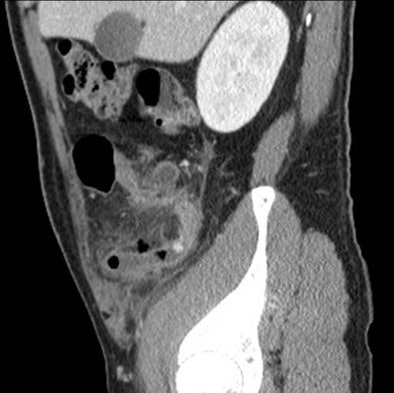

![]() |

| Above, small-bowel obstruction diagnosed with both oral and IV contrast. Below, another patient with small-bowel obstruction diagnosed with IV contrast alone. |